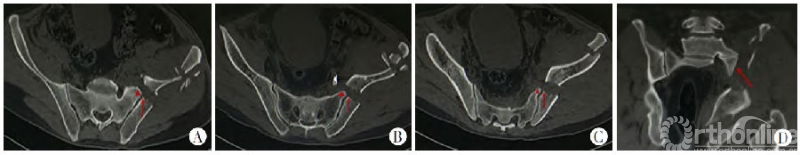

图2 新月形骨折波及骶髂关节的范围有明显的的异质性(图1-4为不同类型的新月形骨折脱位)

Day等[6]总结了16例新月形骨折的特点,将骶髂关节三等分,根据骶髂关节受累的程度将新月形骨折分为3型,并根据不同分型采用不同的治疗措施。

图3

Day分型把骶髂关节均质化看待,将骶髂关节三等分。Day分型的提出对于新月形骨折的认识和治疗有重要意义,但也有其固有的缺陷,仅采用某个层面的CT二维横断面判断骶髂关节损伤程度,并不能反应实际的关节累及程度[6]。Day分型只将骶髂关节三等分,而没有考虑骶髂间复杂的解剖关系及其在侧方挤压暴力下的相互作用;另外在临床应用中会发现Day分型并不能包含所有新月形骨折类型,Calafi和Routt[4]报道这个比例高达12%。

Day等[6]也发现当骨折线为斜形时,通常在不同层面,骨折线进入骶髂关节的位置是不同的,即当骨折线为斜形时,Day分型在不同层面是变异的。不能被分型系统包含或分型的不确定性给治疗带来困扰,也削弱了分型的实用性和有效性[4、5]。